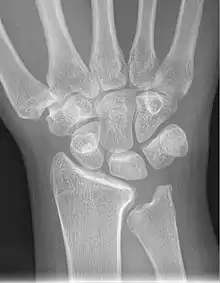

X-ray showing stage IIIB on right wrist, with ulnar impingement.